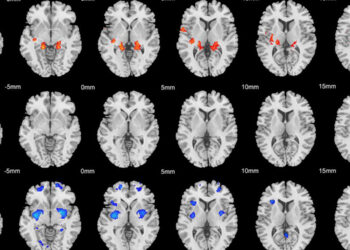

New neuroimaging research offers preliminary evidence that childhood maltreatment amplifies the impact of combat exposure trauma. The findings, published in the journal Military Psychology, suggest that abuse and neglect in childhood sensitizes stress-related brain regions to trauma later in life.

For their study, the researchers used functional magnetic resonance imaging to monitor the brain activity of 28 young adult male military veterans as they completed a mild cognitive stressor task. The veterans also completed scientific surveys about their recent post-traumatic stress symptoms, depressive symptoms, combat experiences, and childhood trauma.

Banihashemi and her colleagues found that childhood maltreatment moderated the effect of combat exposure on neural responses to the task in brain regions associated with cognitive functions, emotional memory, and stress responses.

“Our findings suggest that childhood maltreatment may sensitize anterior and midcingulate brain regions to later life trauma, which may have implications for physiological and behavioral responses to stress and for vulnerability to psychiatric disorders.”